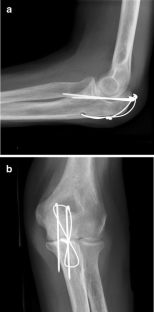

AP and lateral X-rays of a displaced olecranon fracture in a 75 year old female. Positioning of patient supine with elbow pointing upward with a fracture marked on the skin. A drill hole has been made in the more distal ulna for passing of heavy gauge wire for the construction of a figure of eight tension band wire,

Technique of tension band wiring Olecranon fracture Technique A simple transverse fracture can be held accurately by: 1) Inserting a K-wire through the fracture line. 2) Inserting a second K-wire parallel to the first one to prevent

Tension band principles The philosophy behind the tension band for the olecranon is that it converts tensile forces on the posterior side of the olecranon into compression forces at the joint line during flexion. The fixation is simple and inexpensive and works well if executed properly.